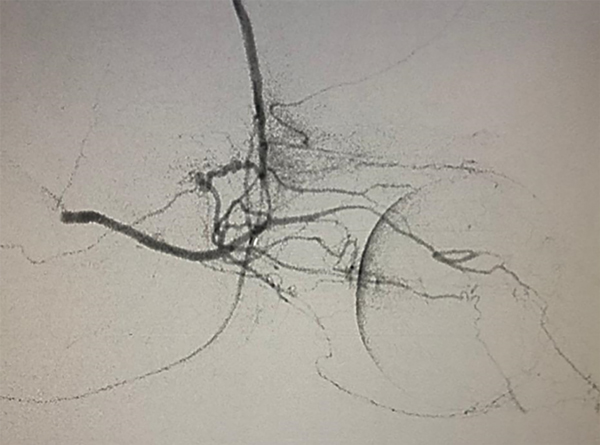

Entre junio 2010 y hasta junio 2021 fueron realizadas 820 sesiones en 176 pacientes (4.6 sesiones por paciente). Todas las intervenciones fueron realizadas por dos neurorradiólogos intervencionistas especialistas. En todos los casos la arteria oftálmica pudo ser cateterizada, 535 directamente (63%) y 285 por vía arteria meníngea media (o meníngea accesoria) con una opacificación coroidea óptima (fig. 1). La principal vía vascular utilizada es la arteria oftálmica con un nacimiento distal al anillo dural (supraclinoidea). De no estar presente o de no poder obtener una correcta opacificación de la coroides por este acceso utilizamos ramos de la arteria carótida externa. La anastomosis entre la arteria meníngea media y la arteria oftálmica está ampliamente descripta en la literatura. Esta comunicación puede darse directamente o a través de la arteria lagrimal o la arteria supraorbitaria. La arteria temporal superficial excepcionalmente puede dar una anastomosis a través de la arteria supratroclear. En nuestra experiencia pudimos corroborar además la existencia de anastomosis entre la arteria meníngea accesoria y la arteria oftálmica, y entre la arteria facial, a través de la arteria angular con la arteria dorsal nasal. La arteria carótida externa es una vía alternativa de gran utilidad ya que presenta múltiples vías de comunicación que pueden ser utilizadas7.

Fig 1: Distribución de las principales vías anatómicas vasculares para quimio-infusión. ACI: Arteria carótida interna. ACE: Arteria carótida externa. El grosor de las flechas es proporcional al orden de frecuencia